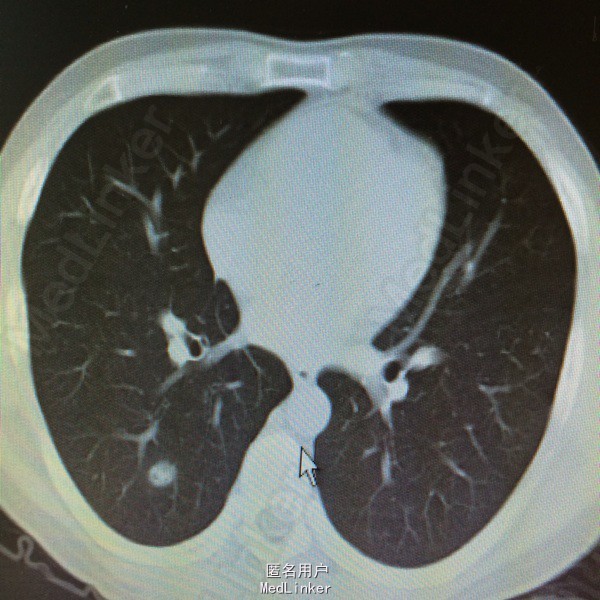

患者因“鼻咽癌放疗后2年余,双肺多发转移治疗后复发2周”入院。详见图片

查体一般可,生命体征平稳,双颈部等浅表未及明显肿大淋巴结,2015.9.15复查ct提示两肺多发转移瘤,较前增多增大。

鼻咽癌肺转移,拟予全身化疗

患者鼻咽癌肺多发转移,目前鼻咽部及双颈部CR,双肺多发转移后予全身化疗及全肺姑息性放疗,放疗后全肺缓解期8个月,未见肺炎。放疗后复发予全身化疗,化疗后缓解期约3个月,现再次复发,但患者血象不宜全身化疗,讨论治疗方案